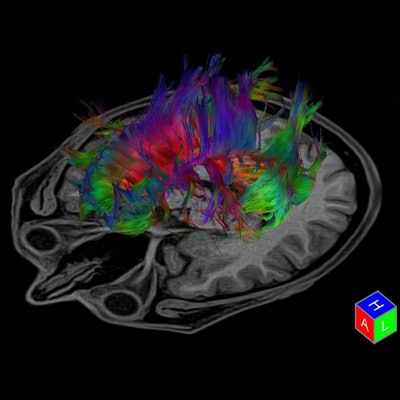

DTI provides qualitative and quantitative information about the microarchitecture of white matter. It can reveal information about the brain microstructure that may not be detected in conventional MR sequences of infants and children with brain malformations. With its ability to better categorize various brain malformations that may look similar on conventional MR imaging but may be caused by different pathomechanisms, DTI may allow transcending MRI from basic anatomic imaging toward function and embryology-based imaging. Conventional MRI is excellent in depicting the big functional centers, the nuclei of the brain. But it does not show how different parts of the brain are connected to each other or if there is an aberrant connection. DTI with fiber tracking does.

"Conventional anatomic MR imaging shows only the tip of the iceberg of microstructural brain malformations. DTI can be quite easily performed in any patient and provide a wealth of information. It is a matter of having the patience, perseverance, and a good knowledge of brain anatomy and function to 'connect the dots' and extract correct and relevant information out of a completed three-dimension tractography reconstruction," he explained.

While powerful postprocessing software programs may identify hundreds or thousands of white-matter tracts within a sampled brain, too many reconstructed fibers can obscure the relevant, aberrant, maldeveloped, or missing white-matter tracts, he added.

Many brain malformations are suspected from prenatal ultrasound data. DTI enables a quantitative analysis, and a structural analysis can be created through postprocessing and reconstructing the course of fiber tracts. As an example, if a neonate is not adequately moving his or her arms and/or legs, the cortical spinal tract can be reconstructed, specifically the fibers responsible for connecting the motor cortex and extremities. Huisman pointed out that it is necessary to know the clinical history of the patient to be able to pinpoint precisely what fiber tracts need to be reconstructed.